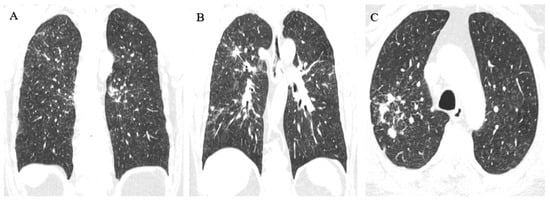

3.1.1. Case 1

3.1.2. Case 2